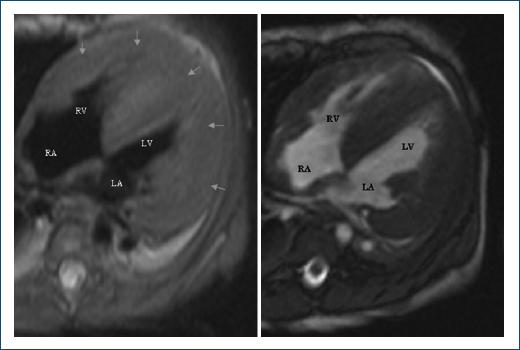

The echocardiogram showed concentric biventricular hypertrophic without and decreased left ventricular function. Late intramyocardial low-septal, middle, and apex enhancement were detected in the magnetic resonance (Figs. 1 and 2). The Genetic screening reported Gene GAA variant c.1987del (p.Gln663serfs*33) compatible with PD. Fifteen days after admission, he died of ventricular fibrillation.

Figure 1 Magnetic resonance in four chambers shows biventricular hypertrophic cardiomyopathy (arrows). RA: right atrium; RV: right ventricle, LA: left atrium; LV: left ventricle.